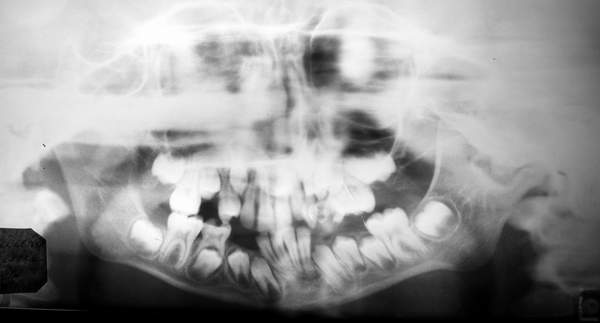

Пациент В., 13 лет. Диагноз: Костный анкилоз левого височно-нижнечелюстного сустава (ВНЧС), левосторонняя микрогения. Болеет с 2-х летнего возраста. Возможная причина развития анкилоза – воспалительный процесс (в первые 1,5 года жизни часто болел простудными заболеваниями, травму родители отрицают). В 3 и 5 лет проводилась редрессация – безуспешно.Прилагаются: ортопантомограмма, кадры СКТ с 3Д реконструкцией. Вопросы: определение тактики лечения – вид и сроки реконструктивно-пластической операции (этапов операции), а именно – неоартропластики и устранения микрогении, медикаментозная терапия в до- и послеоперационный период, ортодонтическое лечение.